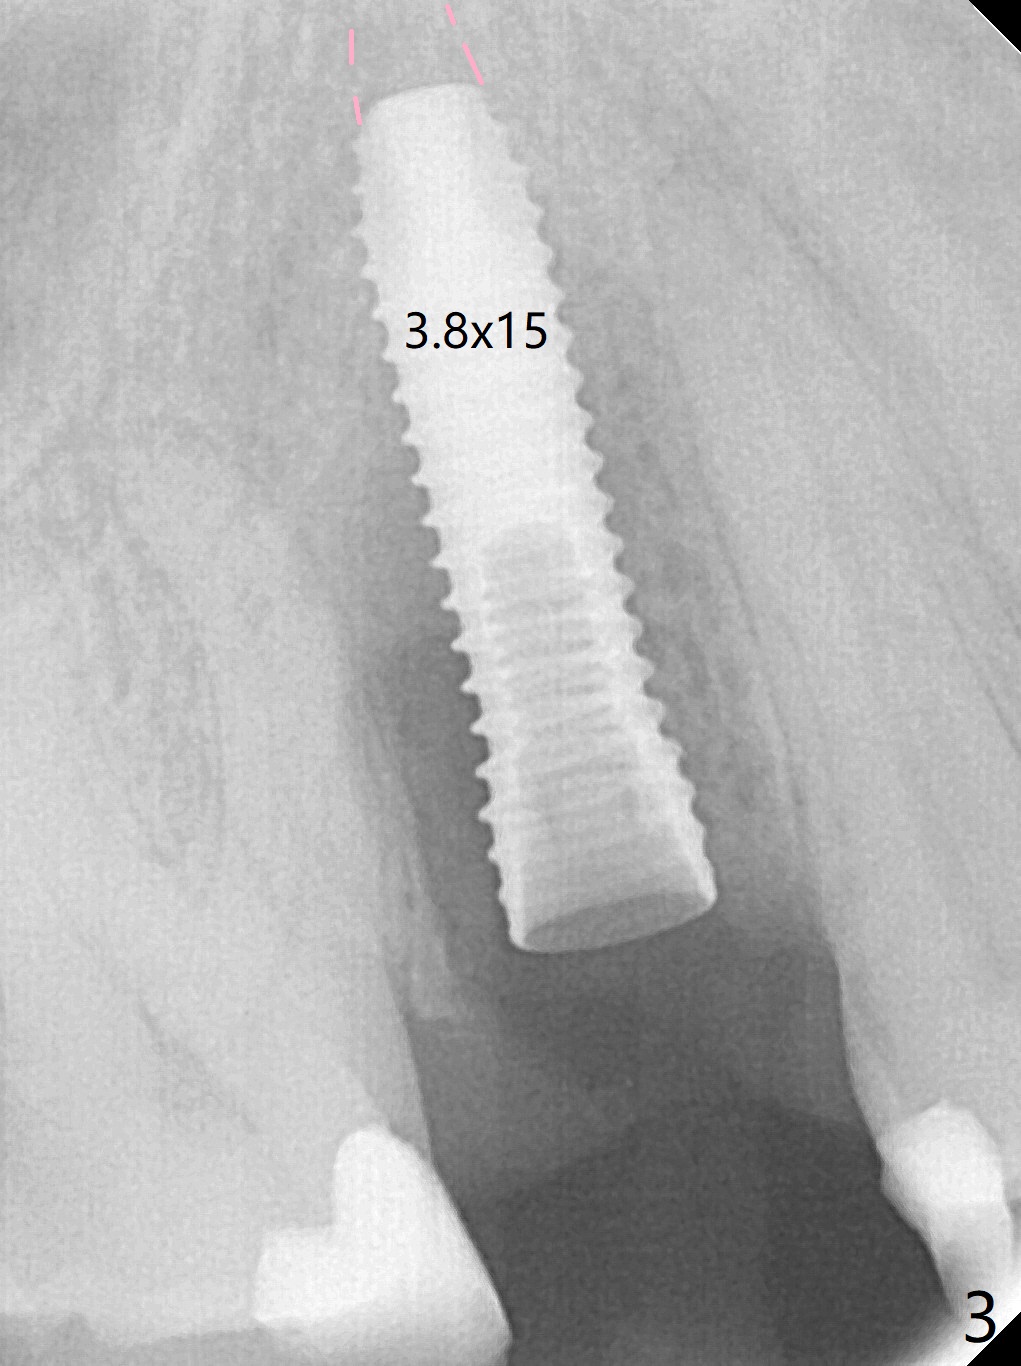

When the tooth #4 with vertical root fracture (Fig.1) is extracted, the buccal plate is found to be lost. The lowest point of the defect is shown as black dashed line in Fig.2 (yellow dashed line: sinus floor). After use of 2.5 mm reamer for 21 mm (buccal gingival level) and 3.0 mm reamer for ~17 mm, a 3.8x15 mm dummy implant is placed with 30 Ncm and 1.85 mm apical space (Fig.3 pink outline). A 3.8x18 mm (definitive) implant is placed with <40 Ncm with the implant plateau apical to the lingual crest (Fig.4,5). The buccal plate defect is repaired by Vanilla Graft (Fig.6 *) before and after insertion of a 4.5x4(3) mm abutment. The buccal plate defect seems to being repaired 4 months postop (Fig.7). Occlusal wear suggests bruxism, which is also associated with the root fracture. Night guard is recommended. The defect repair is close to completion 8 months post cementation (Fig.8). The crown/abutment is found to be loose 1 year 4 months post cementation and retightened without checking whether there is clinical 2nd DO caries of #3 (Fig.9, "sensitive to water pik"). A few days later, DO composite is being removed. It is difficult to determine whether the 2nd DO caries or gap has been removed with the neighboring crown in place. When the crown/abutment is removed and gingival retractions are inserted, there is no decay. The gap is removed. With Toflemire in place, the crown/abutment is reseated and hand tightened; after packable composite, the crown/abutment is removed, there is no more DO gap.